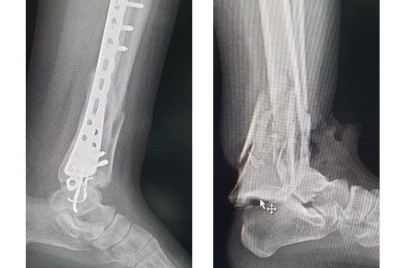

الحدث - محمد العتيق أسهم - بفضل الله - تدخل جراحي ناجح وبرنامج علاج طبيعي تأهيلي أجراه الفريق...